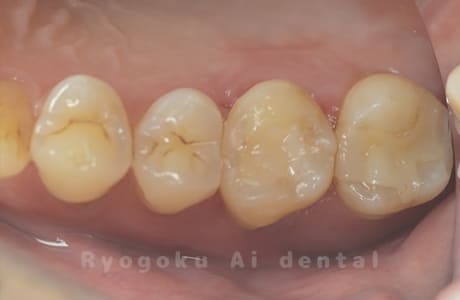

Case03

- 重度カリエス、慢性根尖性歯周炎

- 治療内容

- 自家歯牙移植

- 治療費用

- 220,000円

他院で右下の根の治療を行い、セラミックを被せる説明をされていたが、根の治療が終わらないため転院された患者さんです。隣の親知らずの抜歯の必要性と、根の治療を行なっている歯牙の予後が悪いため、移植治療を提案し、右下の親知らずの抜歯と同時に、右下の奥歯(7番)への移植治療を行いました。被せ物を行う必要もなく、順調に経過してます。

<リスク・副作用>

治療後、痛みや違和感、出血、腫れなどが出る事があります。喫煙者、糖尿病などの方の場合、歯が生着しない場合があります。